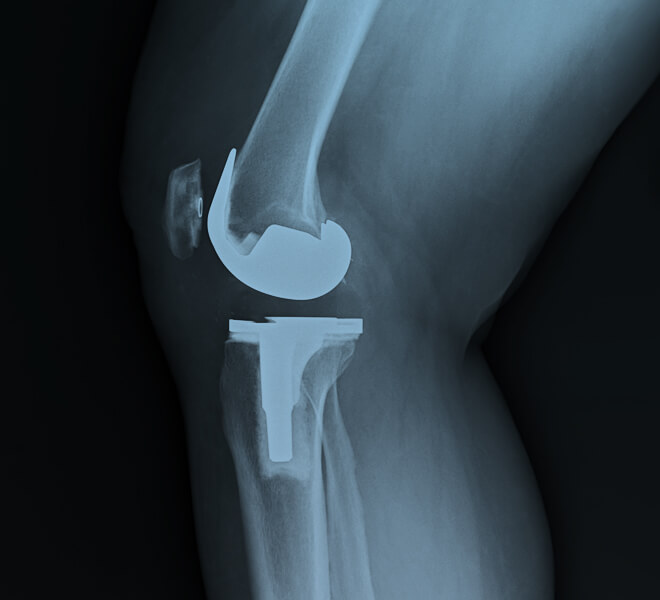

Proteza totale e gjurit (Total Knee Replacement) është një ndërhyrje kirurgjikale ku sipërfaqet e dëmtuara të nyjës së gjurit zëvendësohen me implante artificiale (metal, plastikë të fortë ose qeramikë). Kjo procedurë përdoret zakonisht kur dëmtimet janë të rënda dhe trajtimet konservative nuk japin rezultat.

Përveç shenjave klinike është rezonanca që saktëson gradën e dëmtimit dhe si pasojë nevojën për të bërë një ndërhyrje kirurgjkale për zëvendësimin e pjesës së dëmtuar të gjurit.

- Kirurgu heq sipërfaqet e dëmtuara të kockave: fundin e femurit, pjesën e sipërme të tibias dhe ndonjëherë pjesën e patelës.

- Vendosen komponentët metalikë dhe plastikë që krijojnë një artikulacion të ri.